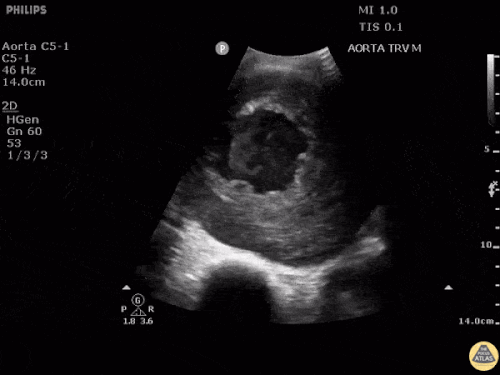

HI-MAP: Aort

Nedeni açıklanamayan şok hastasında, özellikle eşlik eden karın veya sırt ağrısı varsa aort patolojileri mutlaka düşünülmelidir. Bu değerlendirme genellikle büyük bir abdominal aort anevrizmasının (AAA) dışlanmasını amaçlar.

Normal aort çapı 3 cm’den küçüktür. Herhangi bir seviyede çapın 5 cm’den büyük olması, uygun klinik bağlamda akut rüptür olasılığını akla getirmelidir.

Aort en az 4 seviyede görüntülenmelidir ve özellikle infrarenal segment dikkatle değerlendirilmelidir; çünkü AAA en sık bu bölgede görülür. İdeal olarak aortun tamamı kesintisiz şekilde taranmalıdır; ancak bu her zaman mümkün olmayabilir.

Ölçüm:

-

Transvers planda yapılmalıdır

En iyi konveks (curvilinear) prob ile değerlendirilir

Ölçüm dış duvardan dış duvara (outer wall to outer wall) yapılmalıdır

Dış duvardan dış duvara ölçüm yapılmasının nedeni, anevrizma ve diseksiyonun damar duvarı içinde yer alabilmesidir. Bu nedenle ölçüm her iki duvarı da içermelidir.

Hem transvers hem de longitudinal planda görüntüleme önemlidir; çünkü küçük sakküler anevrizmalar tek planda taranırsa gözden kaçabilir.